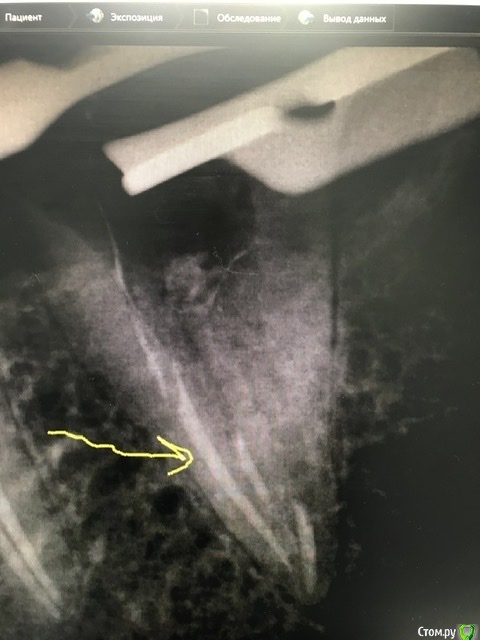

Уважаемые доктора. В 7-ой нижний зуб слева была установлена керамическая вкладка. Началось жжение языка, дискомфорт. Долго думали, решили высверлить вкладку. Ортопед изготовил новую керамическую вкладку, потом решили перелечить каналы, так как нашли дополнительный канал. Затем ортопед установил заготовленную ранее вкладку и зуб начал болеть. Жжение возобновилось и добавилось к боли. Доктор установил временную коронку, корректировал ее несколько раз, так как десна воспалена и в итоге сказал ,если беспокоит надо удалять. Пожалуйста выскажите своё мнение по моей ситуации. Добавляю снимки после перелечивания каналов, после установки вкладки, КТ до лечения. Благодарю за ответы.

post-11530-0-14793000-1600954008_thumb.jpeg

Нужно исключить трещину корня. На снимках она почти никогда не видна (если не явная).